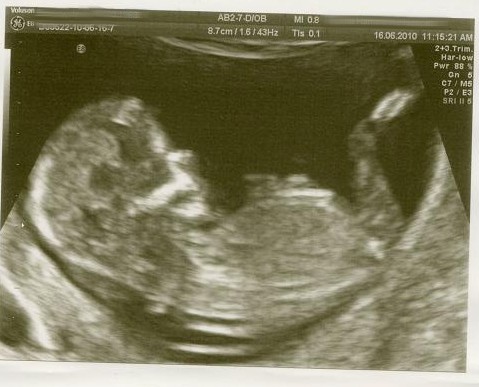

I've attached a pic, of Coulditbemyturns 12 week, confirmed!, nt scan (thank you Couldit xx) Now this to me is a lovely example of what I would look for in a girls skull, a nice semi circle from eyebrow to forehead:)

I've also attached a pic, of my confirmed boy pic, not the clearest of caveman brows, more flat, but you can see that the main height is nearer eyebrow than forehead, causing a flat slope back to the top of the head:) Plus Rainbowflowers (thankyou Rainbow) Ds's nt pic which shows a more flatter forehead but which again would have made me think boy from the lack of any girly curve:)

:DD: GIRL'S

Attachment 811

:DS: BOY'S